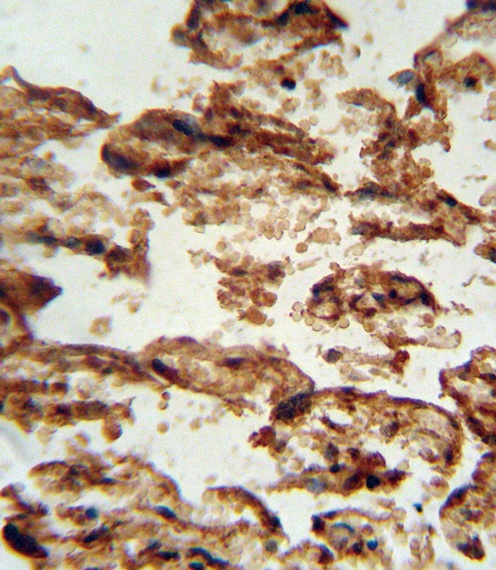

IGFBP4 antibody immunohistochemistry analysis in formalin fixed and paraffin embedded human placenta tissue followed by peroxidase conjugation of the secondary antibody and DAB staining.